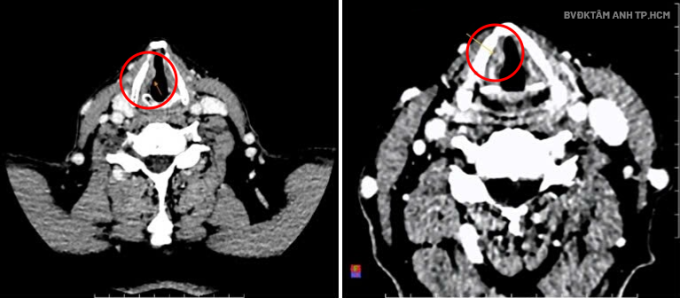

Nội soi tai mũi họng tại Bệnh viện Đa khoa Tâm Anh TP HCM cho thấy hai dây thanh của ông Bình phù nề, dây thanh phải sùi, sụn phễu sung huyết. Kết quả CT ghi nhận tổn thương ở thanh quản, ngang mức ở dây thanh bên phải, dạng sùi, kích thước khoảng 7x14x6 mm. Giải phẫu bệnh xác định ung thư biểu mô tế bào vảy xâm nhập độ hai, giai đoạn T2.

Ảnh chụp CT ghi nhận khối u ở dây thanh phải. Ảnh: Bệnh viện Đa khoa Tâm Anh